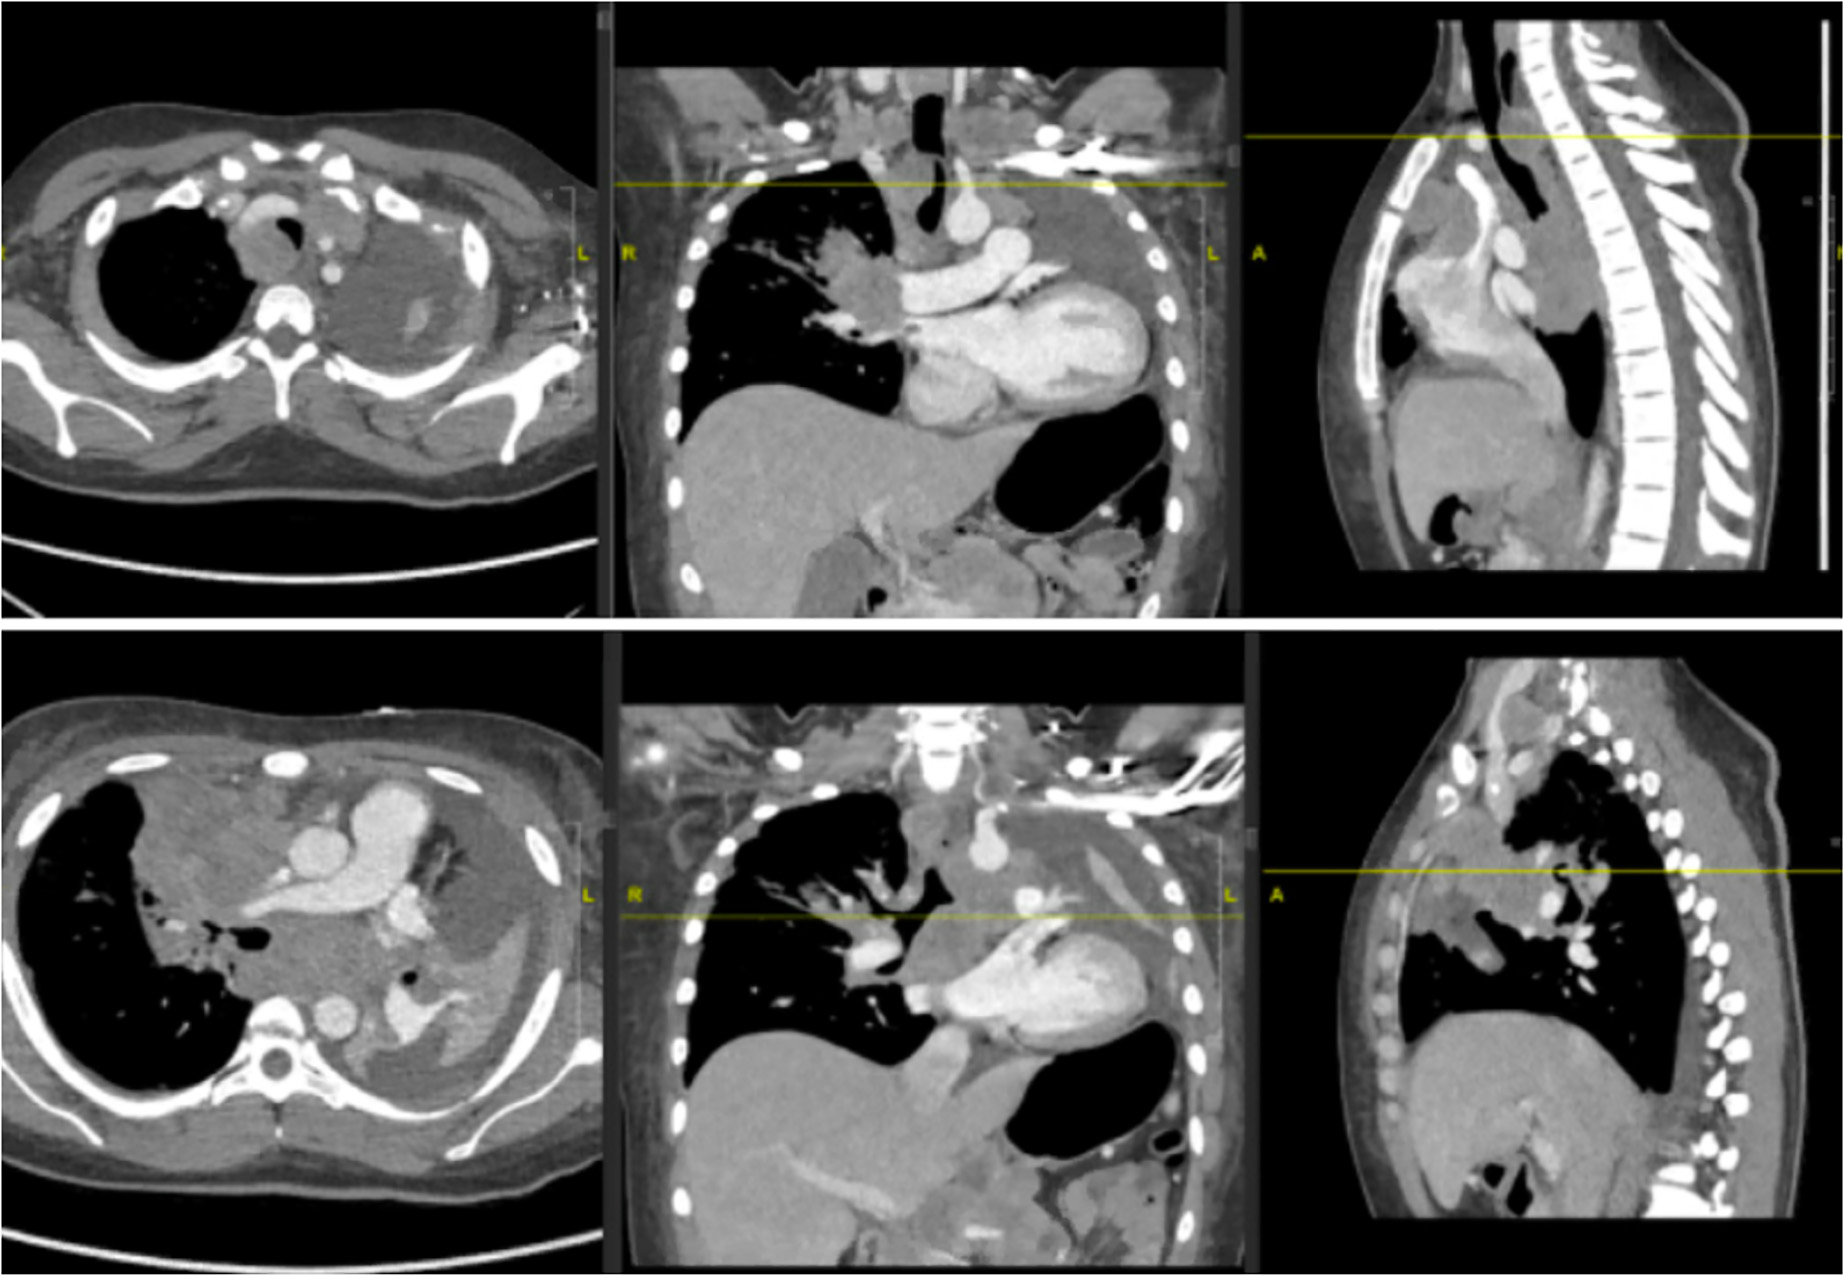

胸片及CT胸部扫描显示右上肺阴影明显增大,下颈部及胸部广泛淋巴结病变,继发于淋巴结病变的左主干支气管完全闭塞,新发完全性左肺不张

伴中度胸腔积液

(图1、2)。

图1 胸片显示右肺门周围及肺上叶病变,左半胸完全浑浊,左半膈抬高。

图2 胸部CT扫描显示右上肺阴影,转移性淋巴结病变,左主支气管闭塞,左肺实变/肺不张。